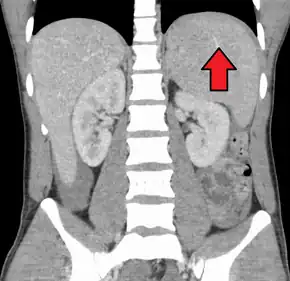

Spleen enlargement is common in the second and third weeks, although this may not be apparent on physical examination. Rarely the spleen may rupture. There may also be some enlargement of the liver.[21] Jaundice occurs only occasionally.[13][23]

Splenomegaly is a common symptom of infectious mononucleosis and health care providers may consider using abdominal ultrasonography to get insight into the enlargement of a person's spleen.[56] However, because spleen size varies greatly, ultrasonography is not a valid technique for assessing spleen enlargement and should not be used in typical circumstances or to make routine decisions about fitness for playing sports.[56]